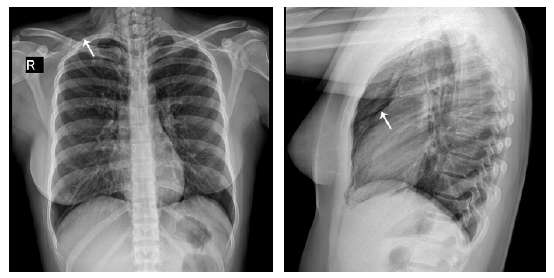

Since pain in the supraclavicular región and right anterior neck was persistent and pneumomediastinum was suspected, a computed tomography (CT) scan of the chest was indicated, confirming pneumomediastinum.

There, air was observed dissecting the mediastinal planes and the base of the neck, with extension to the supra scapular region on the right side; discrete pneumopericardium was also evident (Figure 2).

CT Scan of the chest. => Pneumomediastinum and pneumopericardium.

Figure 2: CT Scan of the chest. => Pneumomediastinum and pneumopericardium.

Source: Document obtained during the study.